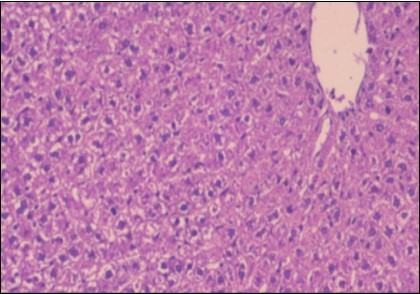

Effect of Ator, Fennel and Their Combination on the Liver of Obese Rats

The histological examination of the livers of control rats feeding standard diet showed normal architecture hepatocytes, blood sinusoid and central vein, figure 6. The rats which were fed on a (HFD), showed swollen hepatocytes with vacuolated cytoplasm filled with fatty infiltration, congested central vein and disappearance of blood sinusoids, figure 7. By comparison, the liver of rats that were treated by fennel after obesity and control mice observed nearly normal of the hepatocytes with eosinophilic cytoplasm, central vein and clear blood sinusoids and more bi-nucleated cells, figure 8. While examination of rats' liver that were treated by Ator and after the obesity appears, they showed mild fatty change in hepatocytes, few hepatocytes retain is eosinophilic cytoplasm and central vein figure 9. Liver of rats that were treated by fennel and Ator after obesity and control rats are showing nearly normal hepatocytes figure 10.

Figure 8.Photomicrograph of liver section of treated rat with fennel herb showing nearly normal of the hepatocytes with eosinophilic cytoplasm, central vein (CV) and clear blood sinusoids and more bi-nucleated cells , (H&E) (40X).

Figure 9.Photomicrogragh of liver section of treated rat with Ator drug showing mild fatty change in hepatocytes, few hepatocytes retain is eosinophilic cytoplasm and central vein , (H&E) (40X).

Figure 10.Photomicrograph of liver section of treated rat both with both fennel herb and Ator drug showing nearly normal hepatocytes (H&E) (40X).